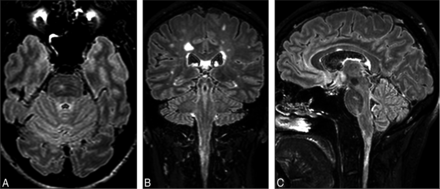

The large FOV of the sagittal 3D acquisition allows good visualization of lesions in the corpus callosum, infratentorial areas, and the cervical spine. In Fig 4, FLAIR2 was calculated on the basis of the retrospectively analyzed patient study protocol. On axial (A), coronal (B), and sagittal (C) sections, an infratentorial, pontine lesion (A and C) and a corpus callosum (C) and a cervical spinal cord lesion (B and C) are visible.

FLAIR2 acquired at 1 × 1 × 1.6 mm3 and reconstructed to 0.51 mm3 shows an infratentorial lesion located in the pons (A and C), a lesion in the cervical spinal cord (B and C), and a lesion in the corpus callosum (C) in the same patient with MS. Due to the isotropic spatial resolution, the large FOV, and the insensitivity to flow in the infratentorial parts of the brain, no additional 2D or proton-density weighted scans are required to visualize these lesions.